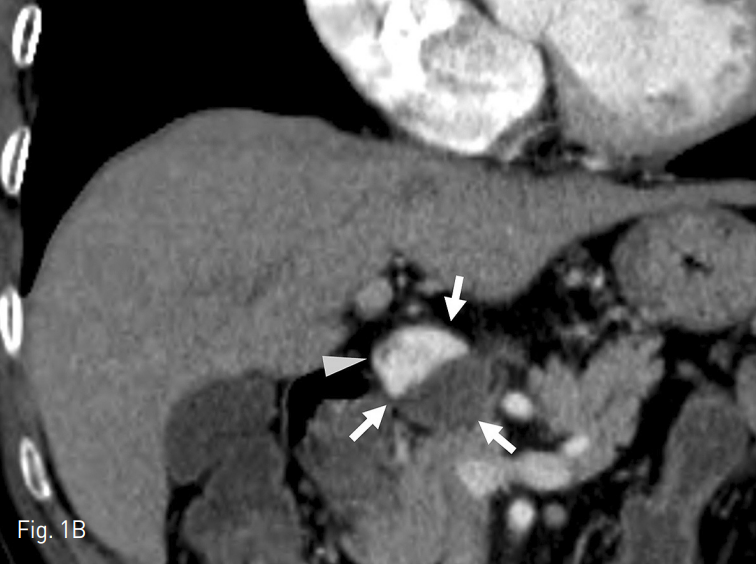

CT에서 proper hepatic artery에 wide neck을 가지고 있는 직경 3cm의 aneurysm이 있으며, 내부는 일부 thrombi로 차있음 (Fig. 1).

Fig. 1

Axial (A) and Coronal (B) CT images showed partially thrombosed aneurysm (arrow) at the proper hepatic artery (arrow head).